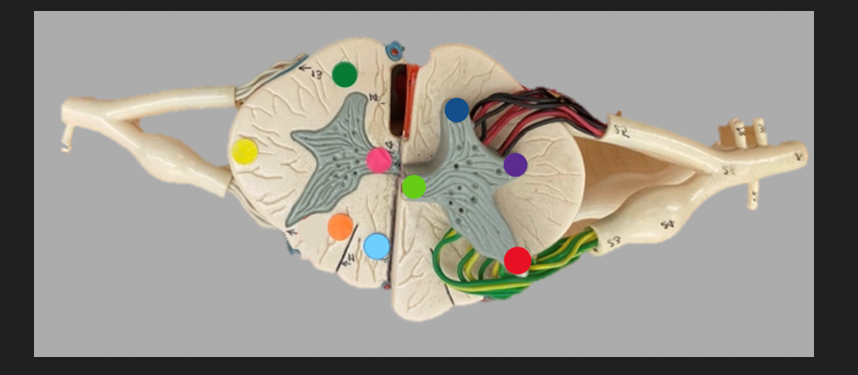

green dot

spinal nerve

orange dot

ventral root

pink dot

dorsal root

blue dot

dorsal root ganglion

red dot

dorsal ramus

yellow dot

ventral ramus

purple dot

anterior median fissure

red dot

posterior (dorsal) horn

purple dot

lateral horn

dark blue dot

anterior (ventral) horn

orange dot

dorsal column

yellow dot

lateral column

dark green

anterior column

line green and pink doit

gray commissure

light blue dot

posterior median sulcus